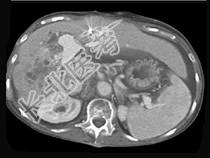

- 单项选择题男,50岁, 右上腹痛,进行性黄疸, 无腹部包块,AFP阴性, 影像检查如图,最可能的诊断为 ( )

D、胆管癌